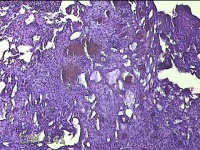

右侧卵巢囊肿

性别

女

年龄

36岁

临床诊断

一般病史

发现双侧附件囊肿1年。

标本名称

大体所见

灰白暗红色囊壁样组织2.5x2x0.3cm一块,表面光滑,部分已切开,囊内容物已流失,囊壁厚0.2cm。

考虑:子宫内膜异位囊肿。